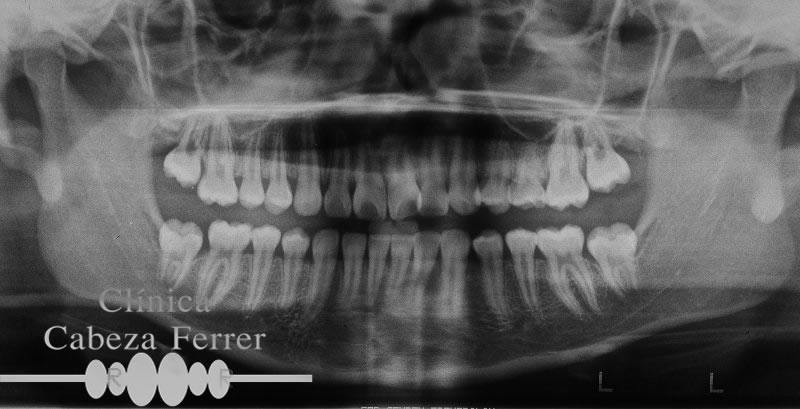

RADIOGRAFÍA PANORÁMICA

La radiografía panorámica (ortopantomografía) se utiliza como complemento de la exploración clínica para la evaluación del hueso, profundidad de las caries, posición de los dientes, visión amplia de la mandíbula, senos nasales, dientes retenidos, tejidos blandos, articulación ATM, focos infecciosos, anormalidades óseas, tumores, quistes, la falta de un diente, planificación y diseño de implantes. Es fundamental para un diagnóstico adecuado y completo.